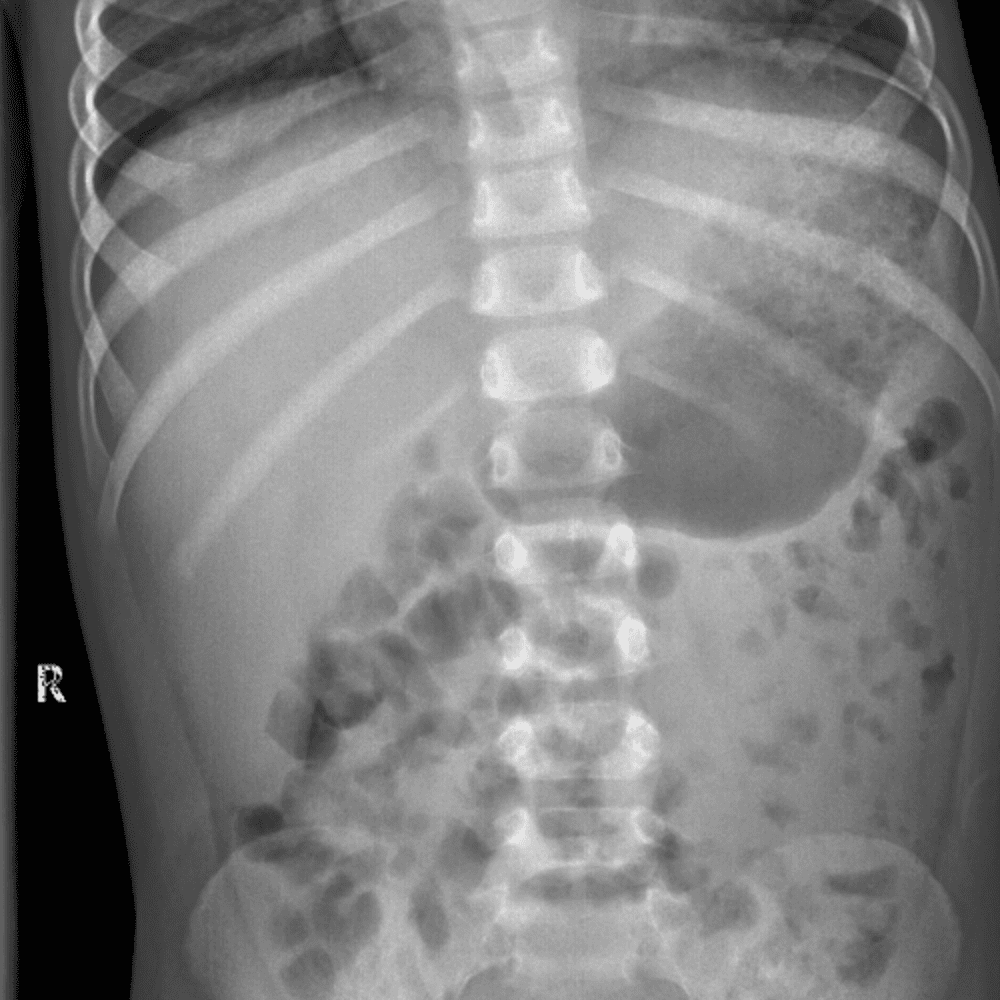

Peds Abdomen

Practice

Simulates call by including subtle or difficult cases and some normals.

30 cases